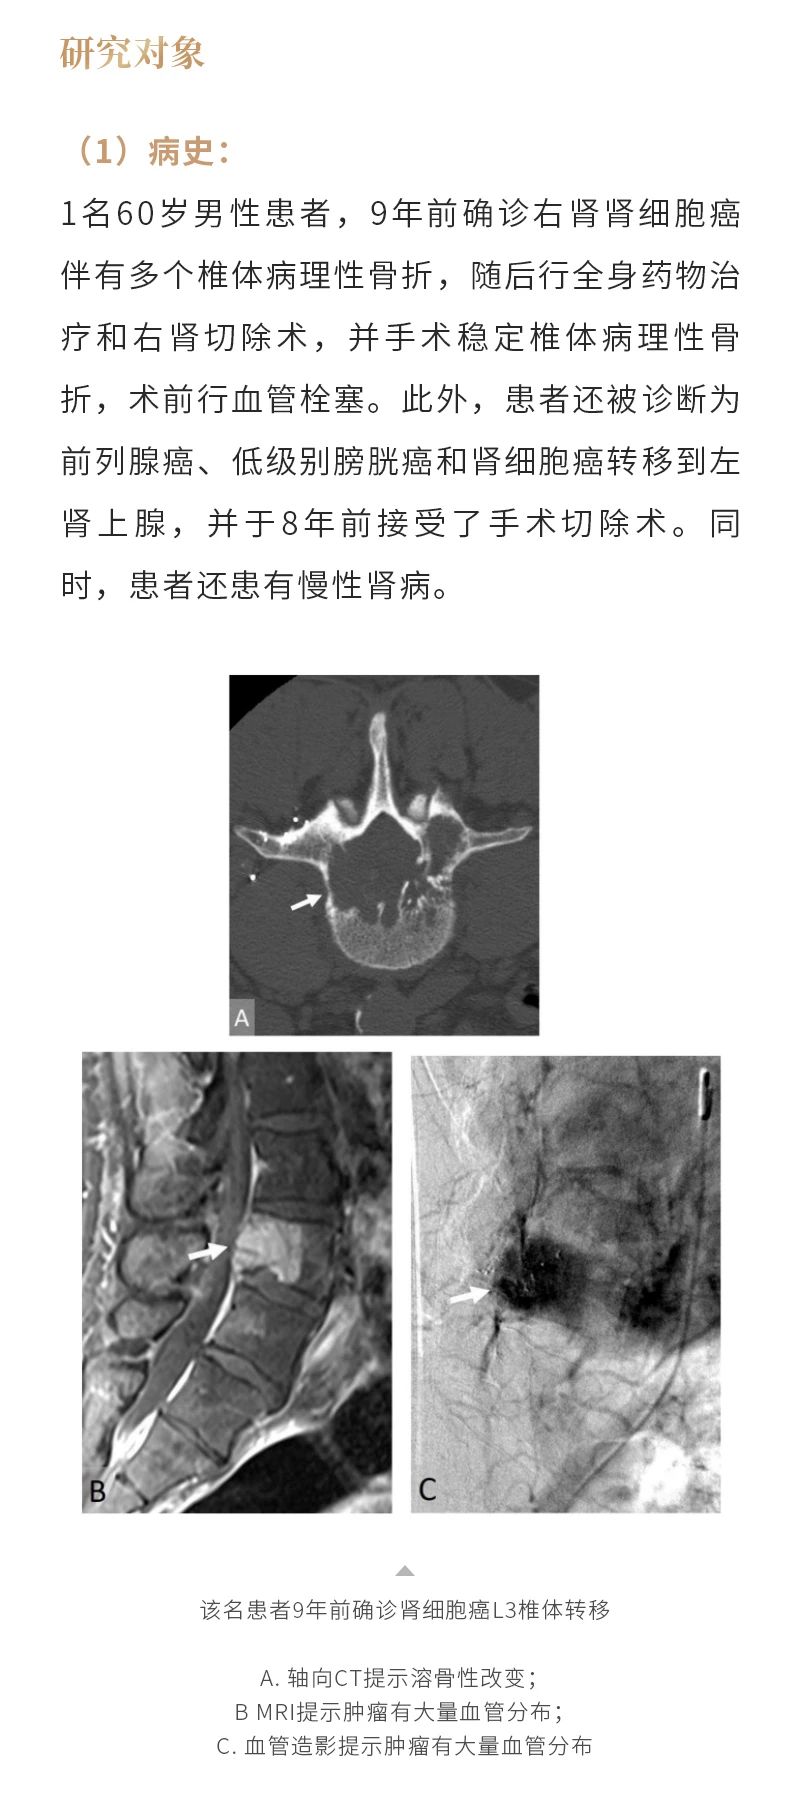

冷凍消融骨腫瘤——【海杰亞科研資訊】第285期

發(fā)布時(shí)間:2024-10-18 | 作者:海杰亞 | 瀏覽次數(shù):1414